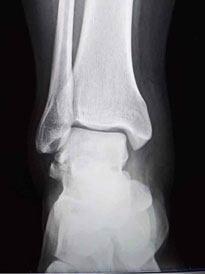

6. What do they look l   ike on X-ray?

Hawkins II

Hawkins II_1

Hawkins II_2